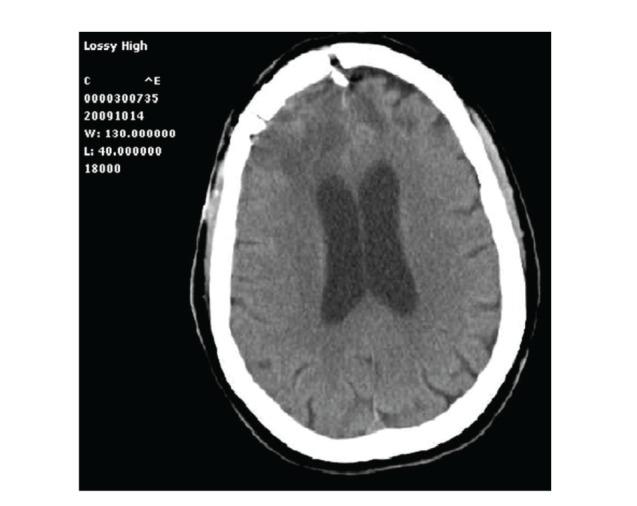

Background. Numerous reports have demonstrated how postoperative intracranial granulomas can often mimic neoplasm clinically, radiologically, and even macroscopically. Herein we present an unusual case of postsurgical intracranial aseptic granuloma secondary to a chronic inflammatory reaction without any identifiable retained foreign body. Case Description. A 71-year-old patient started complaining of severe headache seven months after surgical excision of WHO Grade I right frontal falx meningioma. CT and MRI scans disclosed a contrast-enhanced lesion with diffuse mass effect in the previous surgical site. The lesion was resected; intraoperative finding and histological specimens led to the diagnosis of postoperative granuloma, likely expression of a glial reaction to the fluid absorbable hemostatics applied in the surgical site after meningioma excision. The possible granuloma-inducing materials and the timing of granuloma formation are discussed. Conclusion. A comprehensive analysis of clinical and neuroradiological data, as well as results of blood tests including positive and negative acute phase proteins, is mandatory to raise the suspicion of postoperative granuloma. The treatment options should be evaluated on a case-by-case basis, with a conservative attitude being the one of choice only for patients without progressive neurological deficit. Alternatively, aggressive surgical treatment and histopathological examination should be advocated.

背景。大量报告表明,术后颅内肉芽肿在临床、放射学甚至宏观层面上常常可模拟肿瘤。在此,我们呈现一例不寻常的术后颅内无菌性肉芽肿病例,其继发于慢性炎症反应,且无任何可识别的残留异物。病例描述。一名71岁患者在世界卫生组织一级右额镰旁脑膜瘤手术切除七个月后开始主诉严重头痛。CT和MRI扫描显示在先前手术部位有一个强化病变,伴有弥漫性占位效应。该病变被切除;术中发现及组织学标本诊断为术后肉芽肿,可能是对脑膜瘤切除后手术部位应用的可吸收液体止血剂的胶质反应表现。讨论了可能诱发肉芽肿的物质及肉芽肿形成的时间。结论。对临床和神经放射学数据以及包括正负急性期蛋白在内的血液检查结果进行全面分析,对于提高对术后肉芽肿的怀疑至关重要。治疗方案应逐案评估,对于无进行性神经功能缺损的患者,保守态度是首选。或者,应提倡积极的手术治疗和组织病理学检查。